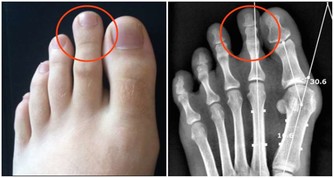

2. 神經根型:是指椎間盤突出或者骨贅壓到了神經根,症狀一般為頸部疼痛,手指麻木、皮膚感覺能力減退,嚴重者還可出現手的大小魚際和骨間肌萎縮。

5. 脊髓型:是頸椎間盤突出或者骨贅壓迫到了脊髓,常見症狀有上下肢無力感,逐漸出現走路踩棉花感,步態拙笨甚至跌倒。後期還可出現排二便障礙。